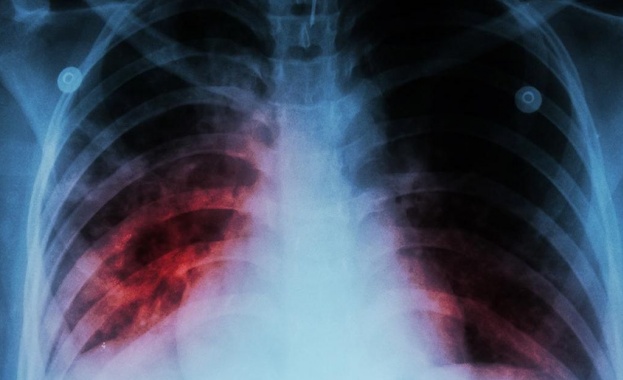

Туберкулоза Над - Новини

...... години от откриването на Mycobacterium tuberculosis - причинител на туберкулозата, от д-р Роберт Кох. На 24 март се отбелязва Световният ден за борба с туберкулозата.

Туберколозата продължава бъде сред 10 те водещи причини за настъпване на

Новите случаи на туберкулоза по света са се увеличили за

...... г. туберкулозата е била на първо място в света по инфекциозни заболявания, но от 2020 г. е на второ място след COVID-19 и преди СПИН.